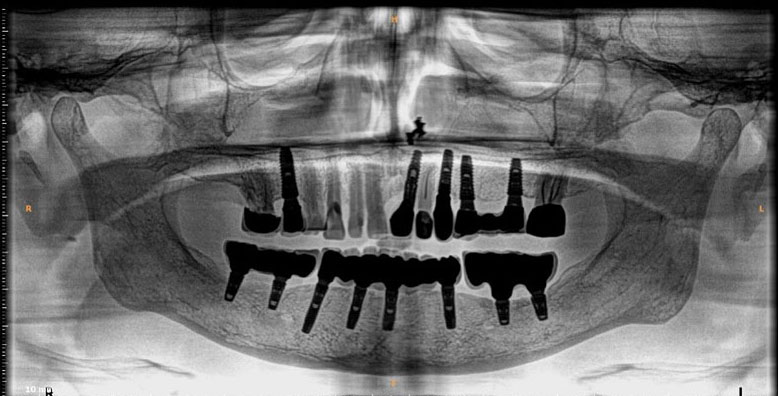

Dental Implants

Dental implants are artificial tooth roots use to replace decayed or missing teeth. They are a popular and effective long-term solution, dental implants are placed into the jawbone, providing a stability for replacement teeth.